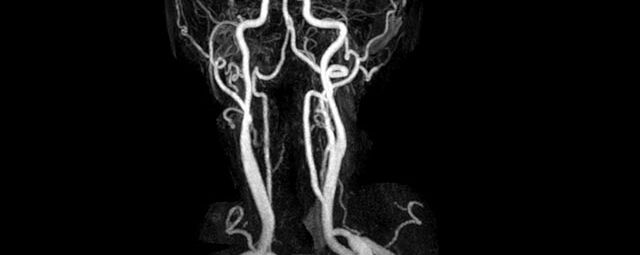

- MR-Angiografie ohne Kontrastmittel

- Time of Flight (TOF)-Angiographie

Je nach Fragestellung und Körperregion Gefäßdarstellung ohne Kontrastmittel bei Kontrastmittelunverträglichkeit oder terminaler Niereninsuffizienz möglich.